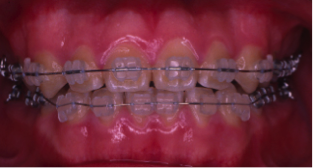

叢生(そうせい)

20歳/女性

悩み:歯がデコボコ

八重歯が押し出されて歯がでこぼこに並んでいる状態

治療期間:約2年4ヶ月

治療前

治療後

奥の歯が倒れて狭くなっている台形の歯列を広げて歯を起こす治療で、奥の歯が見えるようになるUの字型に治しました。

上の歯下の歯、それぞれ2本づつ第一小臼歯を抜歯した治療となりました。

歯を見せて笑えるようになり喜んでもらいました。